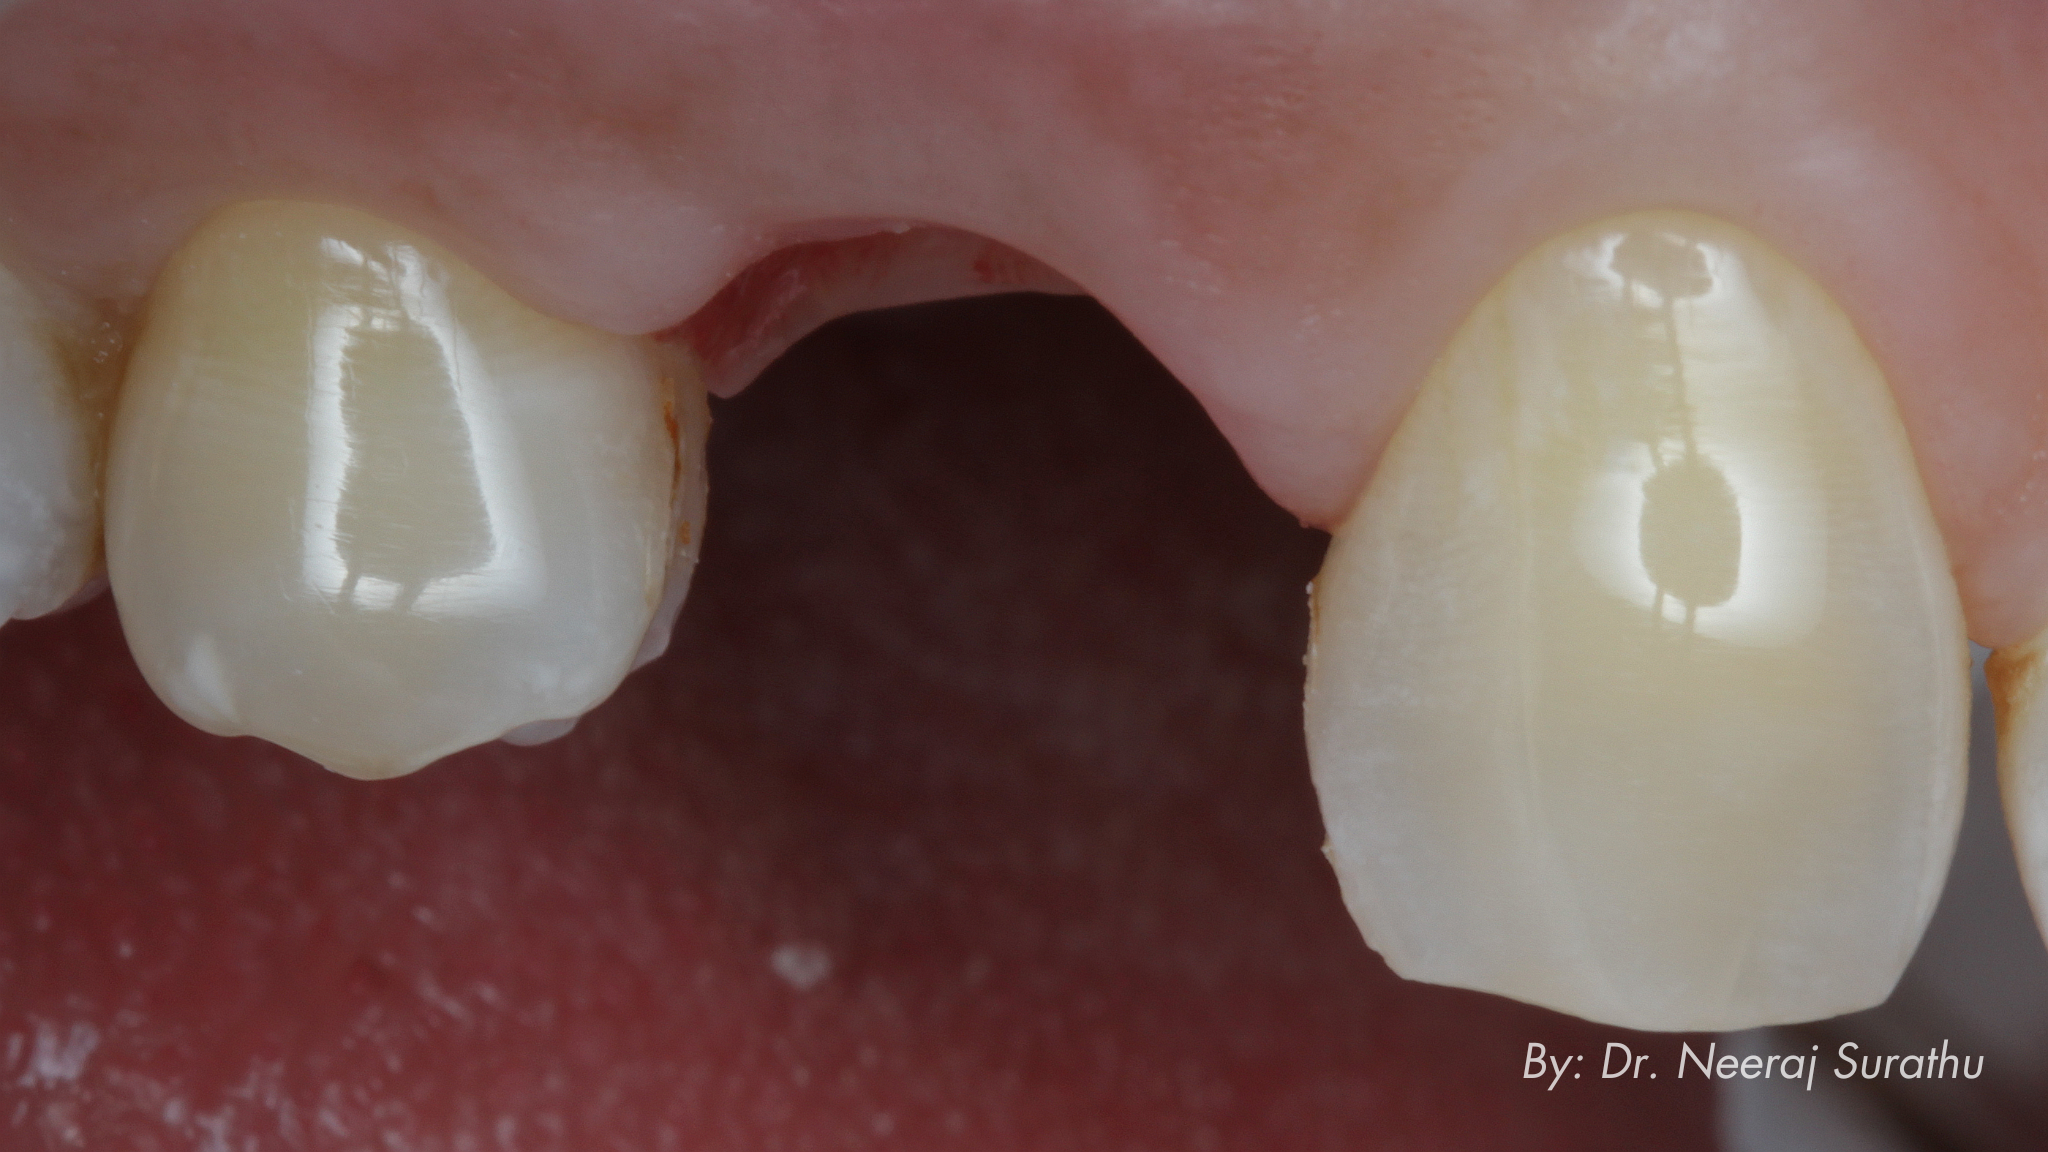

Fig. 12: Three-month post-op image showing healthy tissue with intact papillae, enabling accurate replication of the tissue profile for the definitive restoration.

Postoperative results

The healing of the soft tissue around a polished 3D-printed provisional restoration allowed excellent healing. The provisional restoration was also extremely well tolerated by the tissue and resulted in the development of very healthy tissue, and the position of the papillae was maintained even after the three-month follow-up after implant osseointegration (Fig. 12).